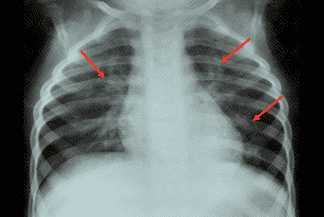

Texto alternativo para a imagem Figura 1. Crédito: Dra. Elazir Mota - Rio de Janeiro/RJ

Descrição da lesão: Radiografia de tórax AP e perfil, evidenciando infiltrado intersticial peribroncovascular bilateral (setas vermelhas) e discreta hiperaeração do parênquima pulmonar.